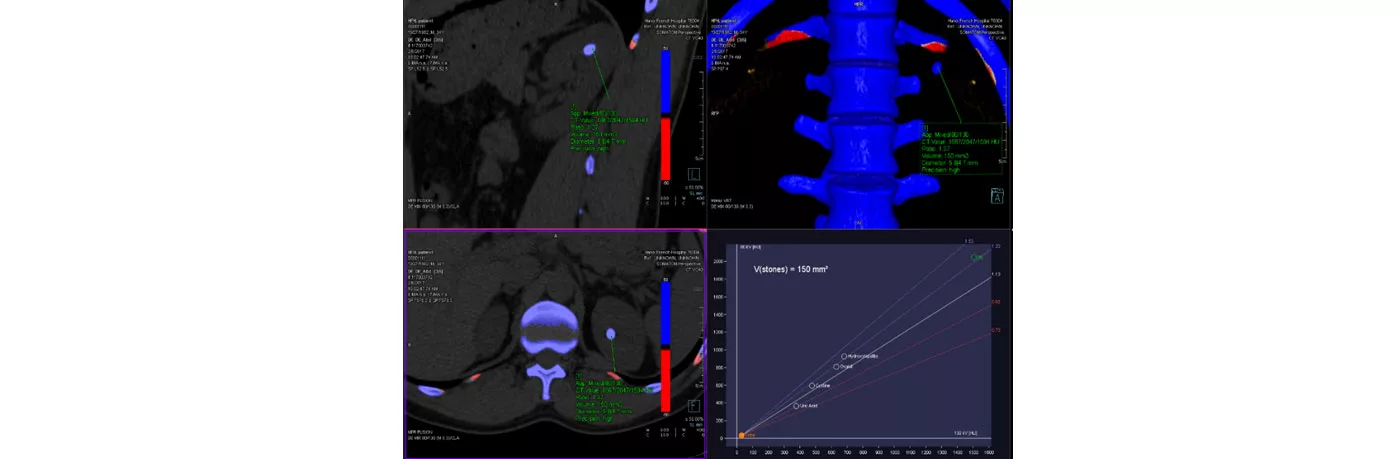

At Hanoi French Hospital, the dual-energy CT scan technology is applied for urinary stone diagnosing, which not only provides physicians detailed information such as the number, size, location, complication, volume of the urinary stones and other urinary system diseases, but also analysis of the urolithiasis’ composition, in the same scan.

This method is considered as a highly accurate non-invasive examination for urinary stone evaluation, as well as time-saving for the examination and result analysis. Then, based to the results, the urologist can provide patients appropriate with advise on how to prevent recurrence of urinary stones.

Image of dual-energy CT scan to evaluate urinary stones at Hanoi French Hospital: